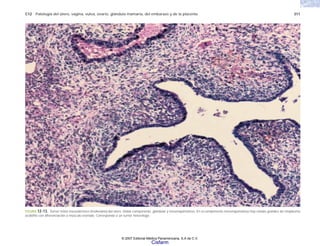

FIGURA 2-1. Glóbulos rojos de un caso de anemia de células falciformes. (Cortesía del Dr. Joaquín Carrillo).